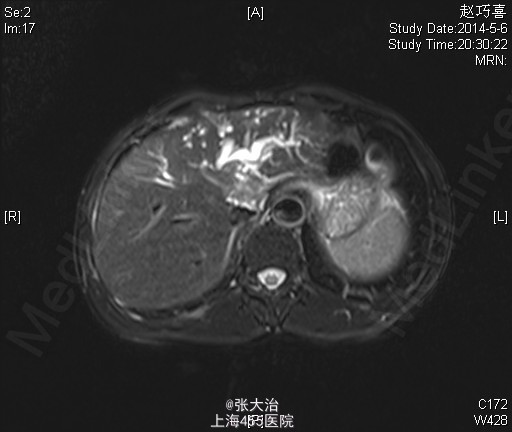

查体:神志清晰,精神尚可,呼吸平稳,营养中等,表情自如,发育正常,自主体位,应答流畅,查体合作。全身皮肤无黄染,无肝掌、蜘蛛痣。全身浅表淋巴结无肿大,无明显贫血貌,左锁骨上淋巴结(-);腹部平坦,未见肠型或胃蠕动波,未见腹壁静脉曲张;全腹软,无压痛、反跳痛、肌紧张。肝脾肋下未及,包块未及;移动性浊音(-),肠鸣音正常,每分钟约3次,不伴高调音、气过水声。 2014-4-10某人民医院就B超(92301):肝囊肿,左肝内胆管扩张;MRI(1697647):肝门区病变可能伴左肝内胆管扩张。 2014-4-22某人民医院MRCP(68941):肝门处占位伴肝内胆管扩张,考虑胆管细胞癌可能大,肝多发囊肿。 肝动脉CTA、门脉CTV、肝静脉CTV、下腔静脉CTVCT【2014-05-05 我院】 :肝门区MT,肝左、右动脉及门脉主干、左支受侵;肝及双肾小囊肿。 上腹部平扫+增强+DWI+MRCPMRI【2014-05-06 我院】 :肝左叶MT(胆管细胞型机会大)伴肝左叶胆管扩张,门脉受侵;肝、双肾小囊肿。 肝脾及门脉;胆(含胆总管);肾+输尿管;胰超声【2014-05-05 我院】 :超声造影:肝门部偏左侧实质占位--考虑肝门部胆管MT,侵犯门脉左支可能;肝左叶胆管扩张;右肾囊肿 肝脏超声造影超声【2014-05-05 我院】 :超声造影:肝门部偏左侧实质占位--考虑肝门部胆管MT,侵犯门脉左支可能;肝左叶胆管扩张;右肾囊肿 肝脏术后(检查胸水、腹水、手术区、膈下)超声【2014-05-20 我院】 :右侧胸腔少量积液;腹水

诊断:胆管肿瘤 治疗经过:患者完善相关检查和术前准备,行剖腹探查,肝十二指肠韧带淋巴结清扫术,胆囊切除 。肋缘下切口逐层入腹,探查肝呈小结节性硬化,色呈粉红。脾脏无殊。胃肠无殊,盆底无转移。先行切除胆囊扩大探查范围。肿瘤位于肝门部胆管,直径3.0cm,累及肝右动脉及其右后分支,累及门静脉主干及右后分支,肝右后叶肝管正常。肝十二指肠韧带背面扪及肿大淋巴结,胃左动脉旁扪及肿大淋巴结,取组织送冰冻病理提示转移。决定终止手术。彻底止血,清点器械纱布无误后逐层关腹。